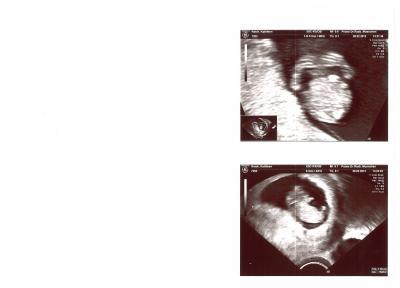

vielen Dank für das Daumen drücken es hat geholfen. Mein kleiner Pukki hat zwar während der Untersuchung geschlafen und sich nicht aus der Ruhe bringen lassen aber man konnte alles schon so genau erkennen. Sogar die Finger konnte man zählen Herz hat auch wie wild geschlagen und meinen MuPa hab ich auch bekommen...und der ist rosa (ob das eine Zeichen ist) Aber egal ich bin so glücklich und erleichtert das alles gut ist. Ich bin laut der Messung heute bei 9+6 und Pukki ist 2,96 cm. Hab nur leider erfahren das ich nicht gegen Toxoplasmose und Ringelröteln immun bin. Und zwei schöne Bilder hab ich auch bekommen. Auf dem ersten ist eine Nahaufnahme und da hat Pukki die Hände vorm Gesicht und man kann da sogar die Finger erkennen... Vielen Dank nochmal an euch...Bussi

Bild zu ihr seid so super - Forum für September - Mamis